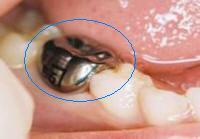

1. Corona inoxidable

1. 6

2. CAVIDAD EXTENSA, DENTINA CLARAMENTE EXPUESTA

1. ACTIVIDAD

1. activida/inactiva

2. HALLAZGO CLINICO

1. Cavida extensa

2. DIAGNÓSTICO

1. lesión cariosa cavitacional con exposición de dentina

1. ICDAS 6

2. TRATAMIENTO

1. operatoria

1. promoción y precvención